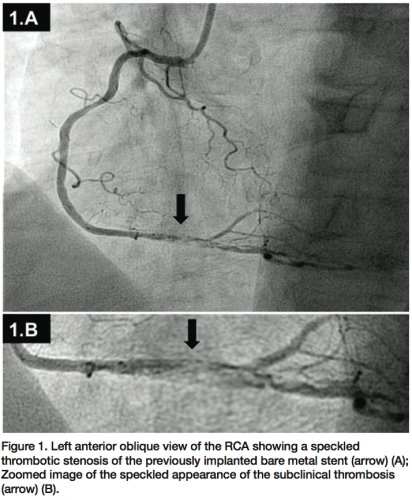

Four weeks later, the patient was referred for elective coronary angioplasty to the proximal first diagonal branch. Dual antiplatelet therapy was administered initially via a nasogastric tube while intubated. He was extubated with minimal residual cognitive deficits, particularly short-term memory and orientation, and no additional signs of ischemia were reported. During the procedure, the previous proximal stenosis in the first diagonal branch was deemed mild after nitroglycerin administration. Thus, a decision was made to review the stent in

the RCA in the same setting. Surprisingly, the stent in the RCA showed a severe, subclinical, and possibly ongoing ST with a particularly speckled appearance (Figures 1A and 1B). This image persisted despite nitroglycerin administration with coronary flow of TIMI II. Following this unexpected finding, a ChoICE PT wire (Boston Scientific, Natick, Massachusetts) was advanced across the stent into the distal posterior descending coronary artery. OCT imaging (DragonFly catheter and C7XR system, LightLab

Imaging) was then performed, showing a “cheese-like” or “spider web-like” structure composed of highly reflective material throughout the stent (Figures 2A–2C). This “spider web-like” occlusive thrombus did not induce shadowing of distal structures and stent expansion could be readily identified. Moderate underexpansion (expansion of 76%) of its distal segment was recognized (measured as the ratio of minimal stent cross-sectional area divided by the mean of proximal and distal reference lumen areas). However, strut malapposition was not detected. Then, an aspiration catheter (ExportAP, Medtronic) was successfully used with improvement of coronary blood flow after retrieval of a large amount of a distinct “white” thrombotic material (Figures 3A and 3B). Finally, the stent was postdilated with a 3.5 x 14 mm Mercury balloon (Abbott Vascular, Abbott Park, Illinois) at 18 atmospheres. Postdilation, OCT showed improved expansion of the stent (stent expansion of 95%) and marked reduction of the thrombotic load, although some persistent thrombus lining apposed to the stent struts was evident (Figures 4A and 4B). An excellent angiographic result with a TIMI III coronary flow was eventually obtained, with mild transient flow deterioration of the posterolateral branch (Figure 5). Clinical course was uneventful and no rise in cardiac markers was detected.

- The angiographic “speckled” appearance (Figures 1A and 1B) that persisted after nitroglycerin administration previously reported by our group as linked to a recent event;11

- A “cheese-like” or “spider web-like” OCT appearance that could correspond to an evolving ST (Figures 2A–2C);

In our patient, OCT examination provided details on the characteristics of the evolving thrombus that showed a pattern formed by multiple tracts of low backscattering protrusions without significant dorsal shadow, suggestive of an ongoing organization of white thrombus. This was confirmed by the histopathology of the material obtained by thromboaspiration. Previous reports have emphasized the unique value of OCT to differentiate red thrombus (with shadowing of distal structures) from white thrombus (without distal shadowing).10 Furthermore, although stent expansion was adequate by angiographic criteria, clear underexpansion and asymmetry of the stent was detected by OCT. Otake et al13 previously showed that underexpansion of sirolimus-eluting stents on OCT could be an important factor in thrombus formation. In the present case, a speckled angiographic pattern and spider web-like projections of white thrombus on OCT, suggestive of either an evolving stent thrombosis or an occlusion-recanalization process, was readily identified. In our previous description of an asymptomatic patient experiencing ongoing stent thrombosis, we found a similar speckled angiographic appearance at the stent site, and a soft, hypoechogenic and obstructive thrombus on IVUS.11 At that time, however, OCT was not available and we failed to fully characterize the pattern of the evolving stent thrombosis. In our current patient, OCT enabled us to recognize a distinct thrombus with cheese-like or spider web-like appearance that suggested a unique phenomenon occurring within the stent. Accordingly, it is tempting to speculate that ST does not occur as a result of a confined, localized, and parietal thrombus lining that increases in size and eventually occludes the stent, but rather from spider web-like thrombus (accounting for the speckled angiographic pattern), initially encompassing only a segment of the stent, but allowing a TIMI III coronary flow, and eventually progressing with obliteration of residual channels and leading to vessel closure.